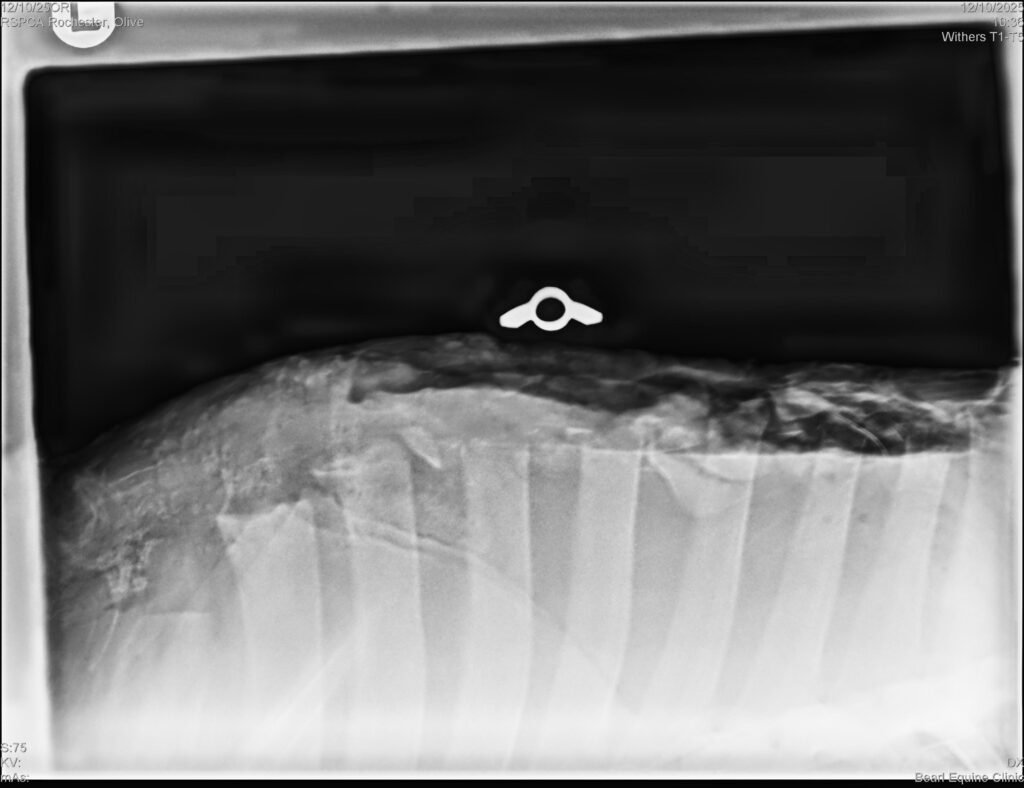

Seven-month-old Welsh filly Olive was discovered by the RSPCA, dumped on a road in Bishop Auckland, with a shockingly deep open infected wound to her withers (the bony spinal processes at the base of a horse’s neck)An abandonment notice was put in place, but again, no owner came forward and Olive was signed over into their care.

Olive required unique and complex treatment, due the significance of the wound, and with the knowledge that Bransby Horses had the facilities and expertise to provide the best possible ongoing care, the RSPCA asked us to take Olive in.

They started by surgically removing unhealthy tissue and placing sterilised gauze into the wound, with cotton swabs tied to the sutures to keep the hole coveredOlive’s dressings were changed every day for weeks and over time her treatment plan was adapted as she began to heal, and the previously large open wound became smaller and shallower. She also needed to eat with her head as low as possible to prevent the top part of her wound from healing too tight.